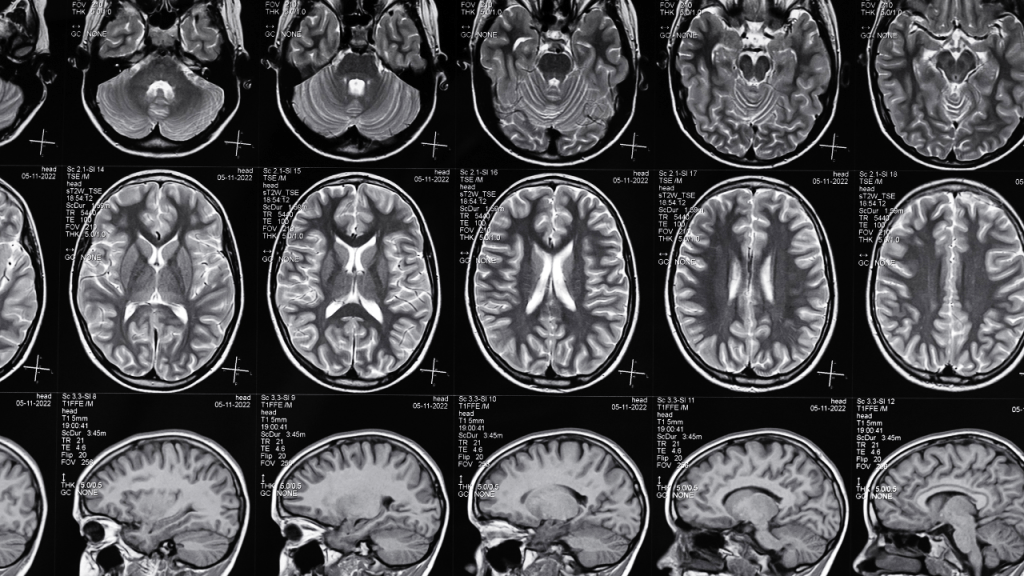

El estudio “Neural correlates of gratitude” (Fox et al., 2015) utilizó resonancia magnética funcional (fMRI) para observar qué partes del cerebro se activan al sentir gratitud. Los resultados mostraron una fuerte activación en la corteza prefrontal medial, el cíngulo anterior y la ínsula, regiones relacionadas con la empatía, la moralidad y la gestión del estrés.